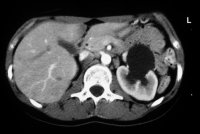

Im Ausscheidungsurogramm und im CT war eine Hufeisenniere mit Pyelektasie links zu erkennen (Abbildung 5).